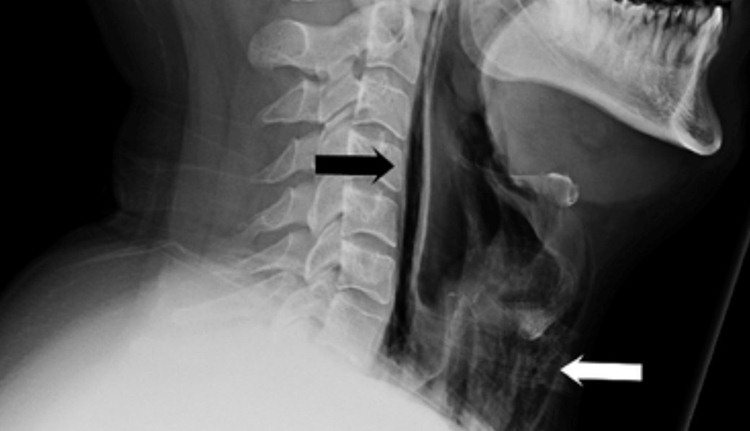

De acordo com Michelle Starr, do site Science Alert, recentemente, um homem de 34 anos foi parar no hospital depois de tentar segurar um espirro cobrindo a boca e tampando o nariz. Após o incidente, ele começou a sentir fortes dores de garganta, dificuldade para engolir, seu pescoço inchou, e o cara perdeu a voz. O diagnóstico? Uma ruptura na faringe, o órgão que conecta o nariz e a boca à laringe e ao esôfago.

Contudo, quando reprimimos uma “esternutação” (olha um nome novo para o seu vocabulário), como foi o caso do homem que tentou engolir o próprio espirro e acabou com a ruptura na faringe, a pressão normal da expulsão de ar pode aumentar em mais de 38 vezes. Basicamente, foi como se a violenta liberação de ar tivesse dado um baita soco na garganta do paciente.

Voltando ao paciente britânico, ele foi hospitalizado para evitar o risco de complicações e medicado com antibióticos, recebeu alimentos através de uma sonda e foi liberado após sete dias de internação.

Mas a situação poderia ter sido muito pior, já que os especialistas explicaram que evitar espirros cobrindo a boca e o nariz desse jeito pode resultar no rompimento dos tímpanos, em um problema chamado pneumomediastino — que consiste no acúmulo de ar no mediastino, que é o espaço que existe no centro do tórax, entre os pulmões — e até na ruptura de aneurismas cerebrais.